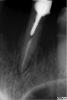

x3m Опубликовано 6 декабря, 2008 Поделиться Опубликовано 6 декабря, 2008 ИМХО - продольный перелом. 100%. Почему:1. на снимке 13 зуба видна продольная трещина (по корневой пломбе, в средней трети корня). Или мне показалось?2. реакция периодонта - непонятная. Не на выведение - точно.3. витки резьбы - активно в дентине корня. Кстати, цемента не видно и за концом анкера.4. анамнез: время возникновения болей - во время посещения, когда фиксировался анкер (реакция на пломбировку и выведение была бы раньше). Пример по аналогии, простите за оффтоп:первичное обращение - март с.г. Жалобы на "запах где-то справа внизу" (обл. 44). об-но - все ок. Десна спокойна. Мысли насчет трещины или нависающего края коронки дистально. . Снимать коронку низзя. "Ну не из-за запаха же ж попадать в перелечивание?!?!" рентген: второе - сентябрь. снимок после удаления коронки и анкера. об-но: см.следующее фото. вот последние фото 44 з.: вид изнутри: ИМХО: анкера - очень нехорошо. в "кривых"руках = зло. ЗЫ Проверьте зондом (острым, не пародонтологическим) корень под десной, если есть возможность. вот прям немного отодвиньте десну гладилкой и проведите горизонтально с вестибулярной и небной пов-ти корня. по идее должны зацепиться, если есть трещина.А вообще - говорить пациентке о планировании удаления. И ориентировать на протезирование - там явно есть показания к этому кроме 13 зуба. имхо. Ссылка на комментарий

spirit Опубликовано 6 декабря, 2008 Автор Поделиться Опубликовано 6 декабря, 2008 Эндо однозначно не очень. Насчёт корня, скорее всего правда трещина или перелом. Я штифт вытащила, времяшку поставила. Пациентка звонила, говорит, что зуб почти совсем не беспокоит. Только если постучать, то ощущается немного. Очень жаль, если придётся его удалить. Пациентка хочет до нового года с протезированием закончить ЗЫ Проверьте зондом (острым, не пародонтологическим) корень под десной, если есть возможность. вот прям немного отодвиньте десну гладилкой и проведите горизонтально с вестибулярной и небной пов-ти корня. по идее должны зацепиться, если есть трещина.А вообще - говорить пациентке о планировании удаления. И ориентировать на протезирование - там явно есть показания к этому кроме 13 зуба. имхо.В понедельник она на приём ко мне приходит, попробую корень пощупать. По моему все таки проблема с эндо,может быть инфицирование стружками на фоне чего и возникли болиЕсли дело в эндо, то почему зуб до фиксации штифта не болел, а забеспокоил уже непосредственно после? Ссылка на комментарий

x3m Опубликовано 6 декабря, 2008 Поделиться Опубликовано 6 декабря, 2008 ...Насчёт корня, скорее всего правда трещина или перелом. Я штифт вытащила, времяшку поставила. Пациентка звонила, говорит, что зуб почти совсем не беспокоит. Только если постучать, то ощущается немного. Очень жаль, если придётся его удалить. Пациентка хочет до нового года с протезированием закончить В понедельник она на приём ко мне приходит, попробую корень пощупать.Если дело в эндо, то почему зуб до фиксации штифта не болел, а забеспокоил уже непосредственно после?Вы уже и штифт вытащили? о, имхо, тогда диагностика упрощается Надеюсь, там не перфо вестибулярной/небной стенки корня? Думаю, чтобы исключить трещину или раскол корня - после очистки канала от остатков фиксирующего цемента (на который анкер садился), на сухие стенки корня нанесите кариес-маркер - если есть трещина - он поможет ее увидеть. И отпишитесь в ветке, как там, в понедельник-то Ссылка на комментарий

Inspiration Опубликовано 6 декабря, 2008 Поделиться Опубликовано 6 декабря, 2008 Эндо однозначно не очень. Насчёт корня, скорее всего правда трещина или перелом . Я штифт вытащила, времяшку поставила. Пациентка звонила, говорит, что зуб почти совсем не беспокоит. Только если постучать, то ощущается немного. Очень жаль, если придётся его удалить. Пациентка хочет до нового года с протезированием закончить В понедельник она на приём ко мне приходит, попробую корень пощупать.Если дело в эндо, то почему зуб до фиксации штифта не болел, а забеспокоил уже непосредственно после?нужно весь цемент убрать,чтобы только дентин остался и все было хоршо видно и покасить,метиленовым синим,фуксином,хоть чем,кариес маркер есть-им,и трещину видно будет,хорошо бы хотя бы бинокуляры Ссылка на комментарий

spirit Опубликовано 8 декабря, 2008 Автор Поделиться Опубликовано 8 декабря, 2008 Приходила пациентка сегодня. Жалоб нет. Вертикальная перкуссия слабо положительна. Проверила я корень со всех сторон. Покрасила кариес-маркёром, "пощупала" зондом под десной, инструментами в канале. Ничего не нашла. Распломбировала канал, поставила метапекс. Так как всё же там периодонтит. К тому же визиограф наш сегодня весь день тормозил Ссылка на комментарий